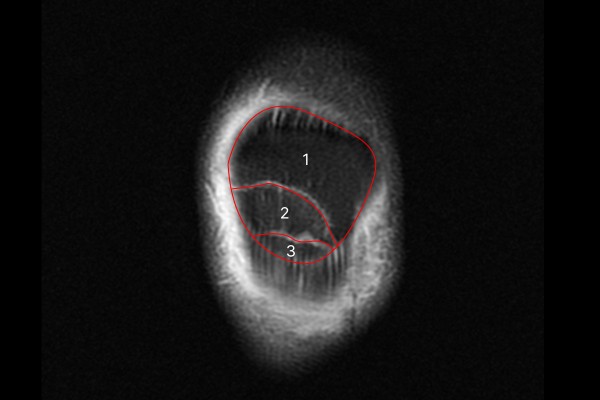

MRI 촬영 결과를 보면 2개의 골절선으로 인하여 슬개골이 3조각으로 나뉜 것이 확인됩니다.

9f695db682e5f1ea0b431dfdec73e7ff_1766564253_1803.jpg

측면에서 확인해봐도 동일하며 우측 무릎뼈 (슬개골) 골절(Fx. patella knee Rt.3)으로 진단하였습니다.